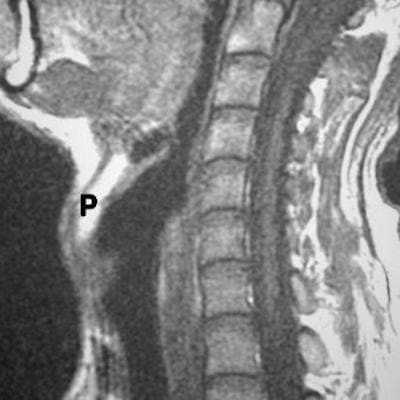

о MPT (Т1 ВИ) лучше всего позволяет обнаружить инфильтрацию основания черепа, отсутствие сигнала, типичного для жира

о Постконтрастные аксиальные и корональные томограммы лучше всего отображают распространение опухоли внутрь черепа![КТ, МРТ при раке носоглотки]()